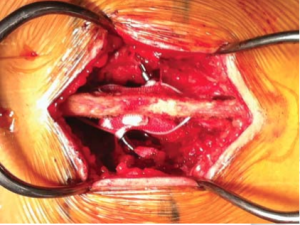

Decompression of L34, L45 and L5S1 were done. L45 through a partial laminectomy of L4 and L34, L5S1 through limited interlaminar approach. L45 was stabilsed with rigid fixation and fusion using pedicle screws, L34 with a dynamic interspinous devices and L5S1 was decompressed only.

This patient illustrates one of many patterns in patients presenting with lumbar spinal canal stenosis and the available options in surgical treatment. Decompression is necessary to relieve nerve compression. Additional procedures often aim to treat back pain or prevent further deterioration and recurrence of symptoms. The commoner options include fusion and soft stabilization. To treat back pain and to prevent deterioration of the spondylolisthesis, L45 fusion was done. At L34, an interspinous device using silicone-based implant allows assisted motion and helps to maintain an open foraminal canal. At L5S1, the small sacral spinous process makes the interspinous device interspinous device ineffective and as fusion was not yet needed, only a decompression was done. DIAM (Medtronics)

In this case, the interspinous implant used was a DIAM (Device for Interspinous Assisted Motion). Such devices are designed as an alternative to fusion in sutable cases. The DIAM is a silicone based implant inserted between the spinous processes in to allow assisted motion of facets, unloading of the disc and maintain the patency of the intervertebral foramina. The device is kept in place by the retained supraspinous ligament and anchors to the spinous processes.